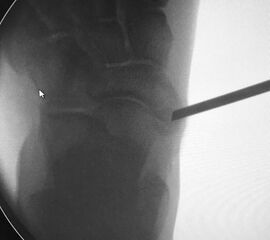

- Intra- und postoperativ Röntgenkontrolle Fuß in 2 Ebenen zur Dokumentation. Operational zusätzliche 3 Ebene in 45° Supination.

- Fehllage des Knochenankers. Die korrekte Platzierung des Knochenankers wird unter Bildverstärker in 2 Ebenen kontrolliert und dokumentiert.